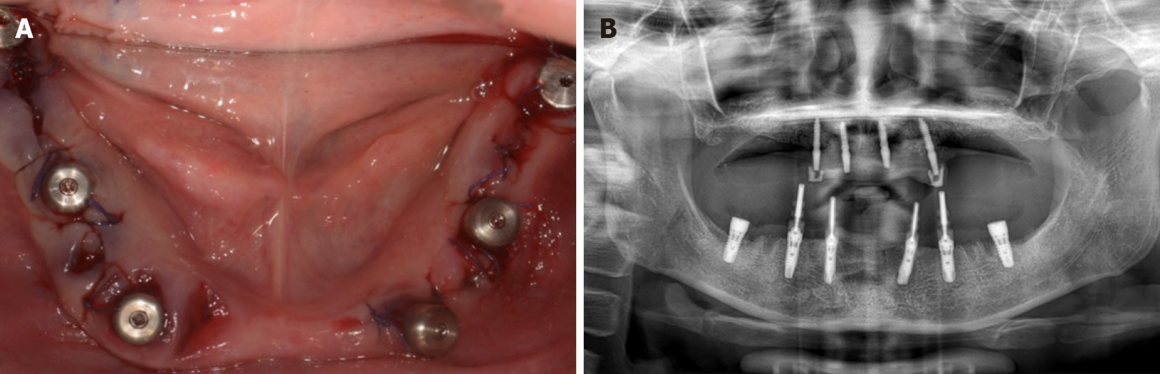

Тотальная реабилитация

Проблема: Отсутствие зубов